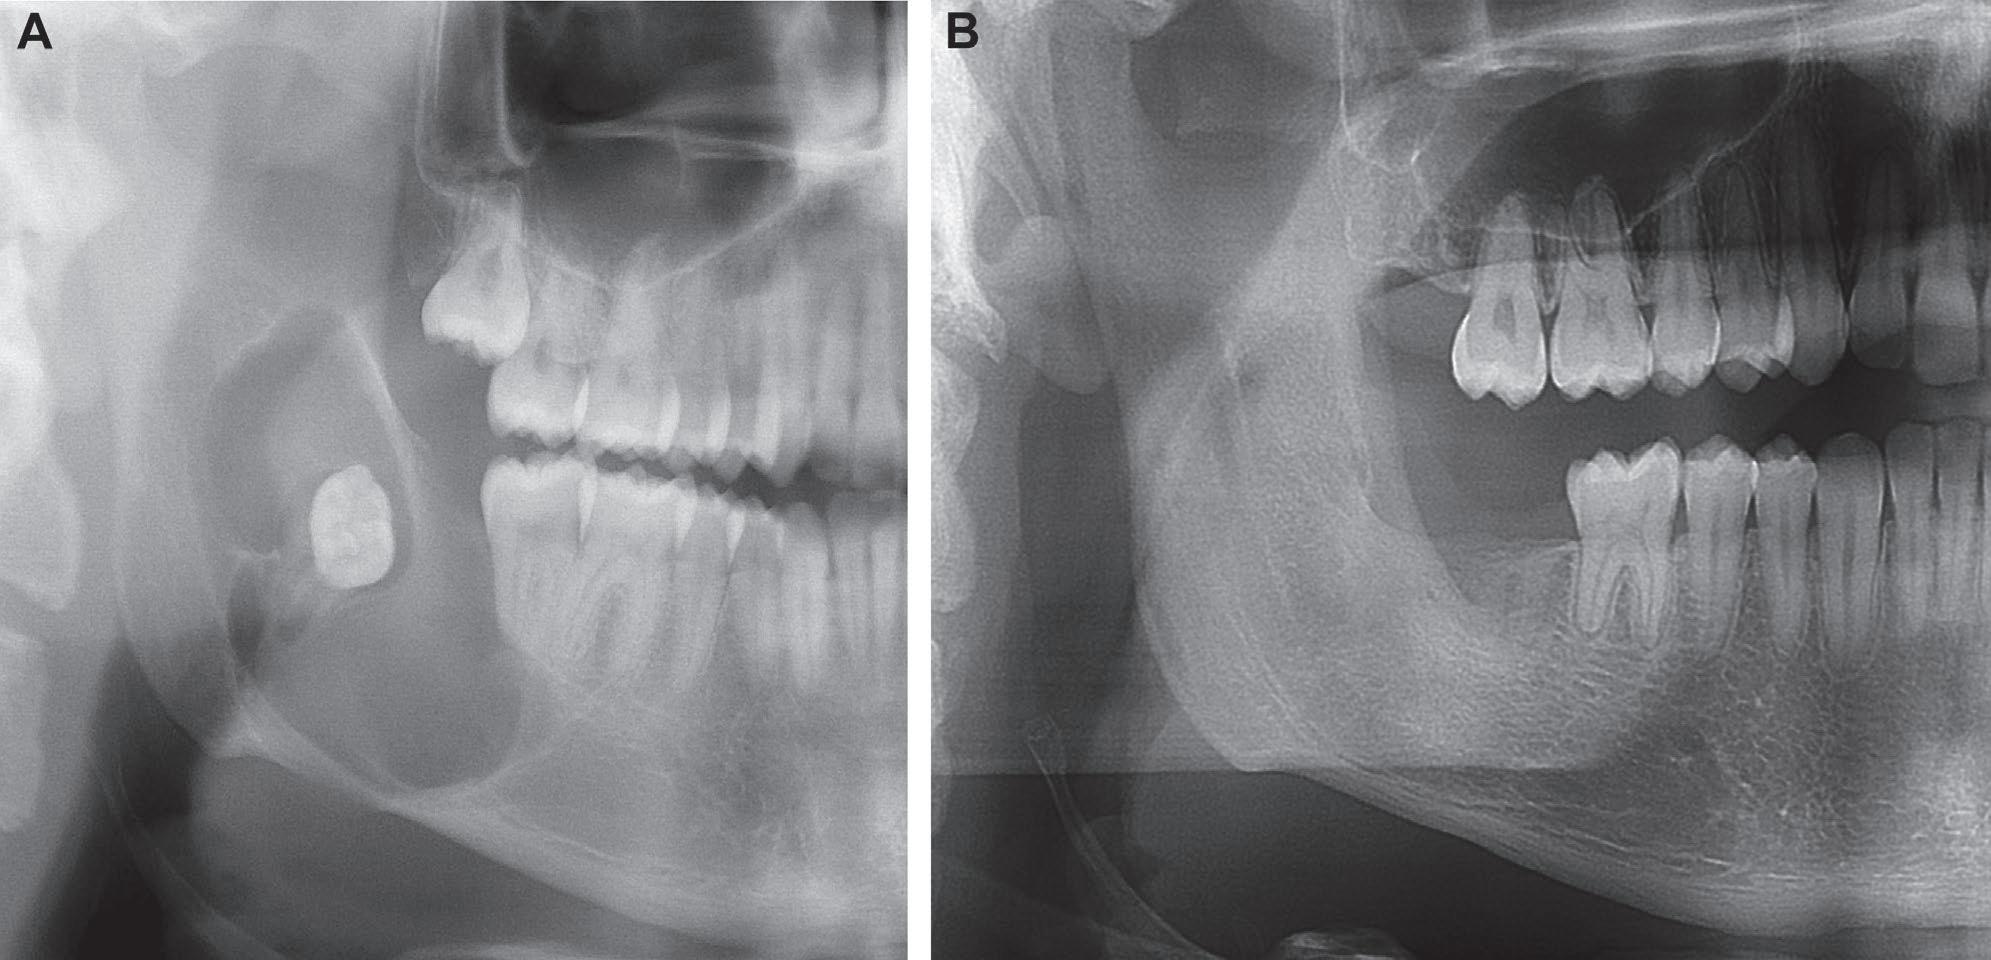

Representative example of odontogenic keratocyst treated with refined topical 5-fluorouracil technique. A, Preoperative Panorex radiograph showing a biopsy-confirmed odontogenic keratocyst involving the right mandibular body, and ramus. B, Six-month postoperative Panorex radiograph showing a well-healed, cystfree right mandible treated with enucleation, peripheral ostectomy, and refined topical 5fluorouracil technique.